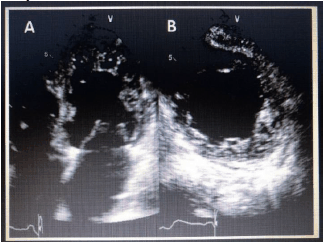

De acordo com a patologia presente na imagem adquirida abaixo, assinale a alternativa correta.